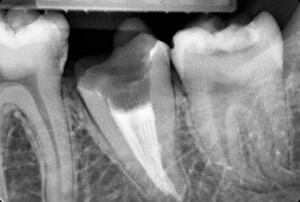

Клинические случаи в эндодонтии